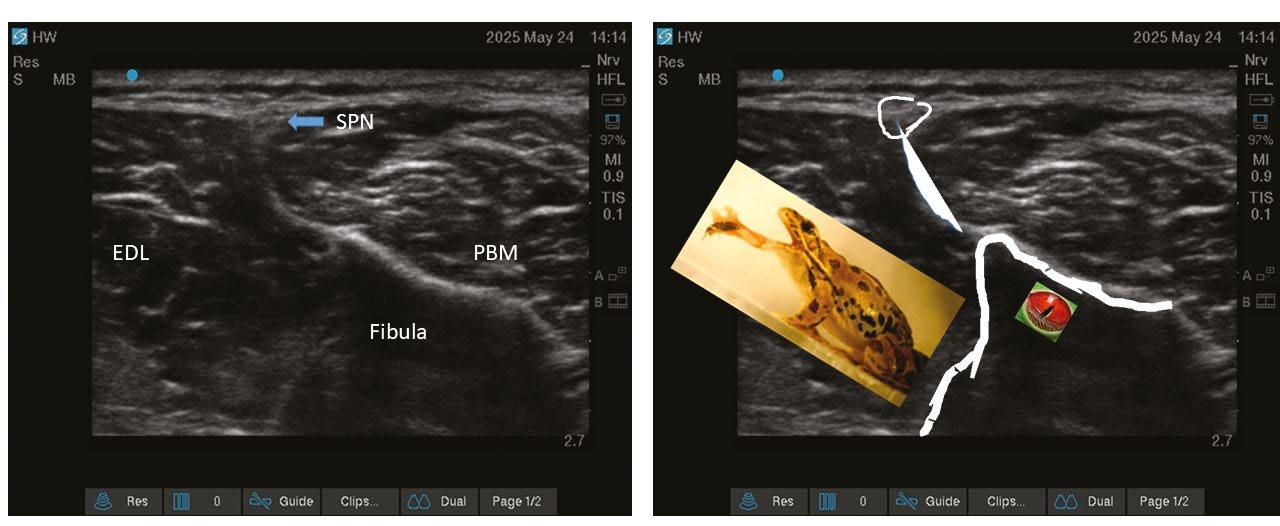

Another focus for AI in anaesthesia lies in real-time analysis of ultrasound scanning.[8] Multiple algorithms have been developed to segment and apply colour to greyscale ultrasound live images. Despite promising progress, the evidence base gathered to assess and appraise the utility of these various tools remains insufficient. Studies are too heterogenous, use differing performance metrics and ground truth definitions, or are simply not made public due to commercial sensitivity.[9]